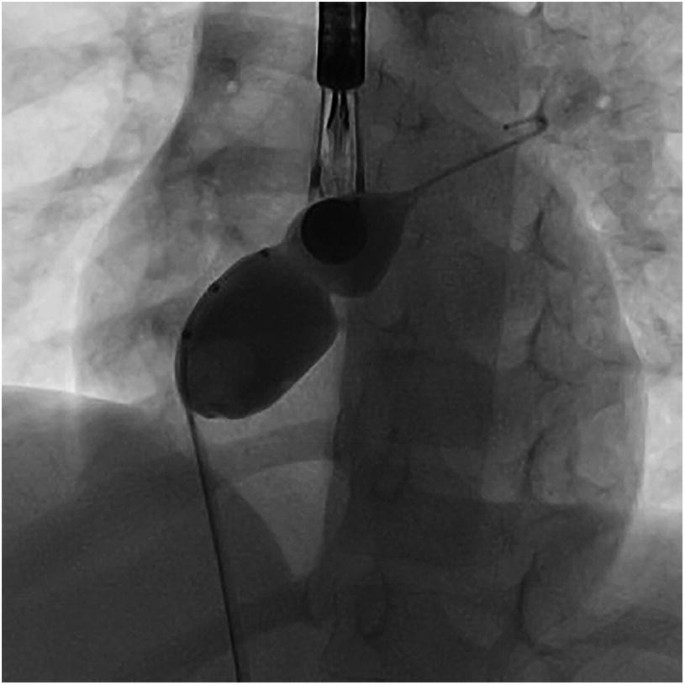

Existen diferentes tipos de marcapasos provisional, cada uno con características y aplicaciones específicas. El marcapasos cutáneo-torácico, también conocido como marcapasos externo, es un sistema de alta energía que se aplica directamente en el tórax en situaciones de emergencia. Por otro lado, el marcapasos endocárdico es un sistema de baja energía que utiliza impulsos aplicados a través de un electrodo posicionado vía endovenosa. Finalmente, el marcapasos epicárdico es un sistema de baja energía que aplica los impulsos directamente sobre el epicardio durante una cirugía cardíaca.